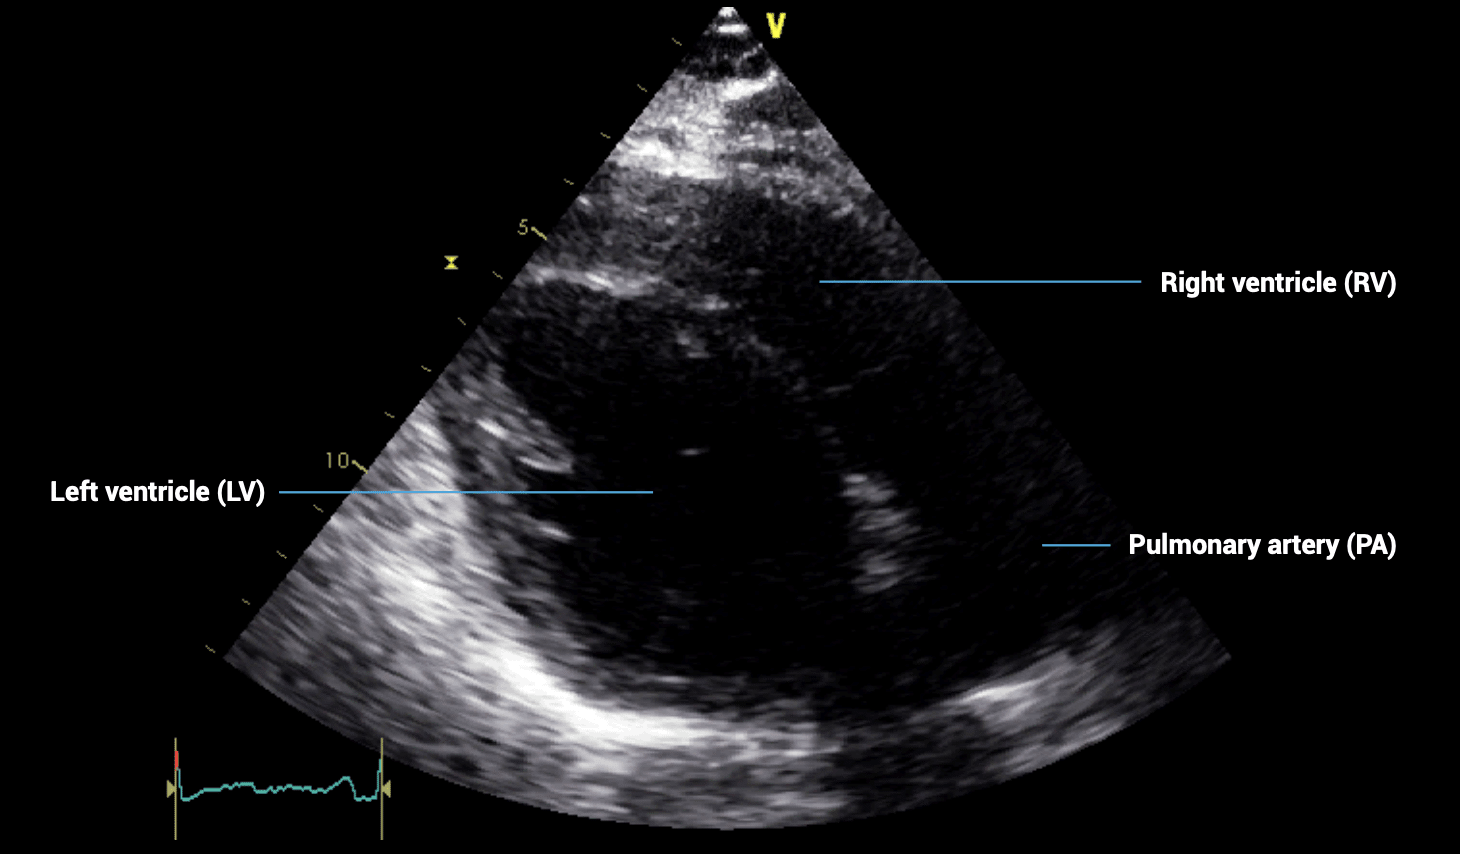

PARASTERNAL LONG-AXIS (PLAX) VIEWS – Obtaining an optimal image

- Patient position: lying on left side, left arm raised, raise the back of the bed or use pillows under the left shoulder

- Probe position: 4th intercostal space, left sternal edge

- Probe orientation: notch towards patient’s right shoulder